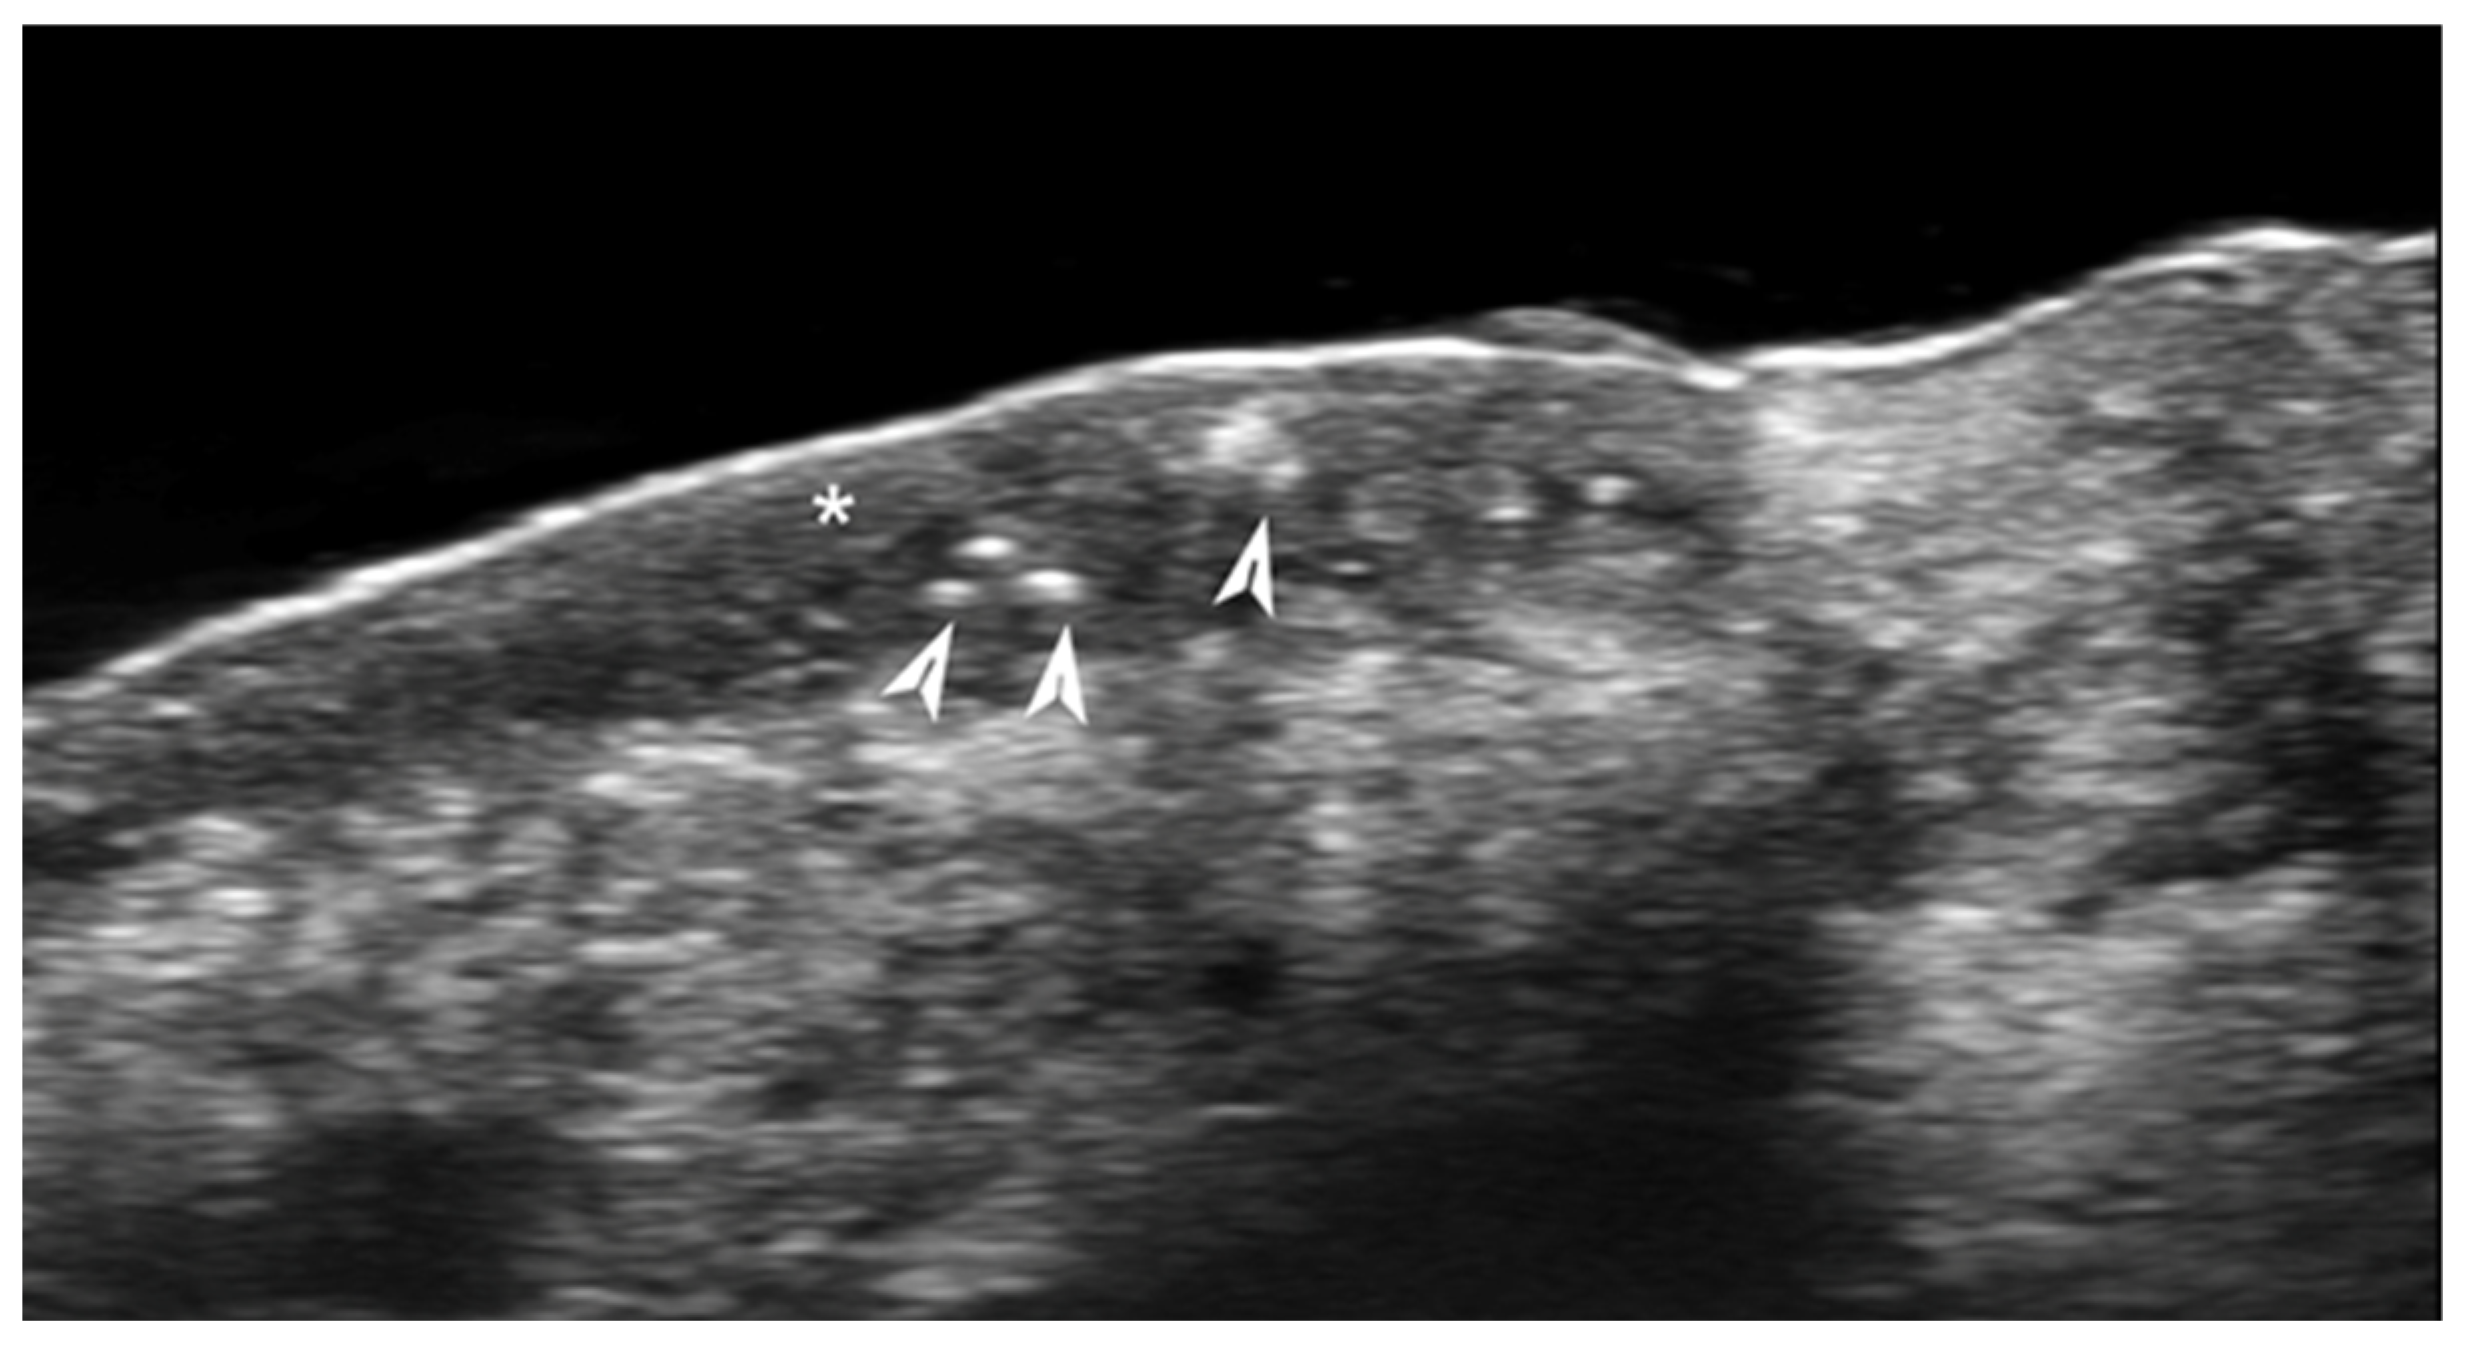

- Ogueta, I.; Navajas-Galimany, L.; Concha-Rogazy, M.; Álvarez-Véliz, S.; Vera-Kellet, C.; Gonzalez-Bombardiere, S.; Wortsman, X. Very High- and High-Frequency Ultrasound Features of Cutaneous Larva Migrans. J. Ultrasound Med. 2019, 38, 3349–3358. [Google Scholar] [CrossRef] [PubMed]